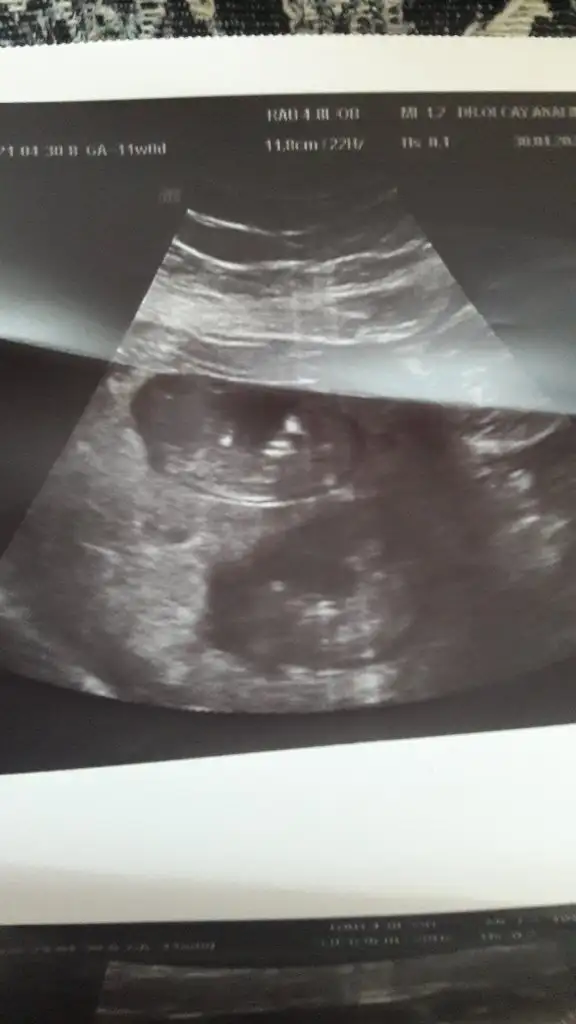

Merhaba cinsiyet tahmininde bulunabilirmisiniz acaba doktorum önce kız sonra erkek dediEki Görüntüle 2839553

Hanımlar tecrübeli anneler cinsiyet tahmini yapabilir mi acaba

16 haftalık doktor önce kız sonra erkek dedi kafamız karıştıEy yarabbi bide arkasını dönmüş

bence erkek bacak arasında yumurtalıkları var gibi

Yaaa çok tatlımaşallah bencede erkek ama hiç anlamam ara boş gibi değil